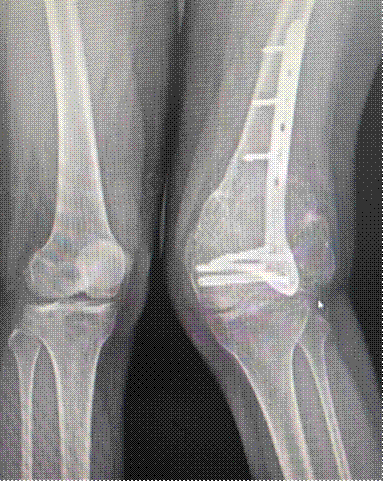

患者范女士(30岁)两年前因右股骨远端病理性骨折于外院行手术治疗,术后病理诊断为侵袭性骨巨细胞瘤,术后两年复查发现右侧股骨远端肿瘤复发,局部压迫症状明显,外院建议行截肢手术。

术前x线表现

对于这突如其来的噩耗,患者一时难以接受,后慕名来到同济大学附属同济医院骨科门诊就诊。经过周密的术前检查及评估发现,患者股动脉尚未被肿瘤完全包绕,这为保肢手术创造了良好的条件。近期,在同济医院骨科创伤骨科主任樊健教授的指导下,骨科李山珠主任医师、蔡涛博士团队完整切除了病变的股骨远端肿瘤并安装新型的铰链式人工膝关节假体。手术十分顺利,术后X片显示患者膝关节功能良好,目前正在康复中。

术后影像